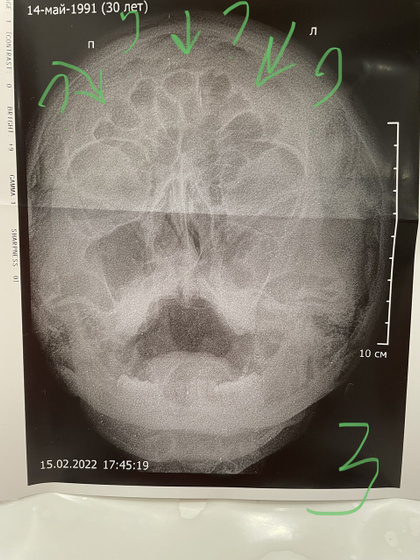

На моем снимке (3) непонятные дольки выделенные (стрелками отметила). Это вообще что всё такое? Капец мне пришёл?